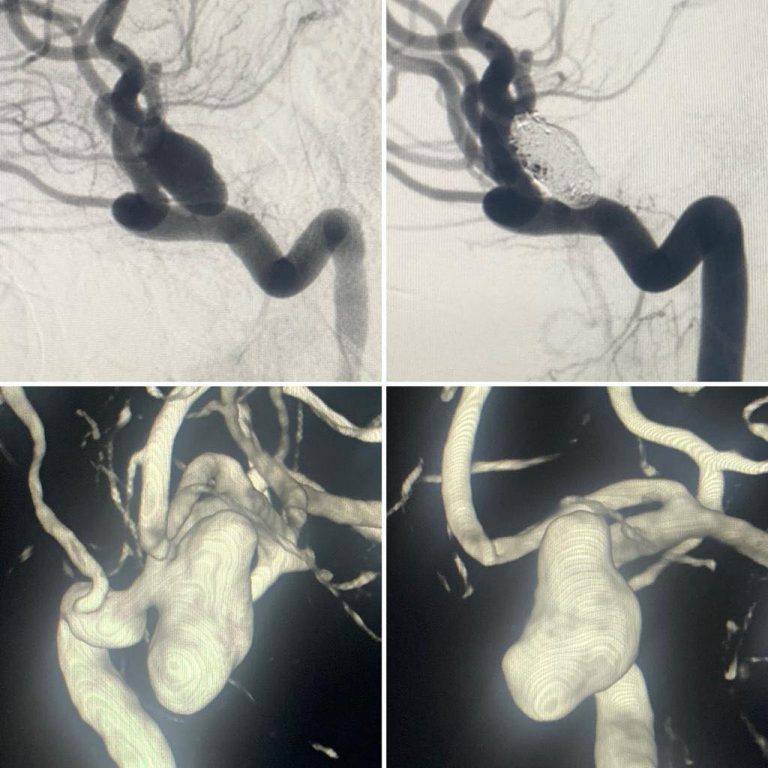

Снимки и иллюстрации микроаневризм сосудов головного мозга